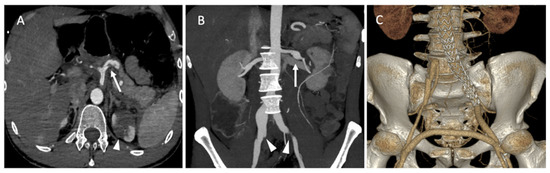

A 35-year-old male patient was admitted to the emergency department for acute abdominal pain. The CT scan showed a celiac trunk dissection extended to the hepatic and splenic arteries, a left renal artery dissection with an infarct and a right common iliac artery dissection with an aneurysmal formation (Figure 8A). The patient was monitored in the intensive care unit and treated with antihypertensive and analgesic anticoagulation therapy and strict rest. His clinical phenotype indicated vEDS according to the vascular medical team, and celiprolol was introduced. Four days later, he presented with recurrent abdominal pain associated with severe lumbar pain. A CT scan demonstrated a rapid diameter evolution of the left renal artery aneurysm and right common iliac artery dissection and a new dissection of the left common iliac and right renal arteries (Figure 8B). The pain regressed with blood pressure control and analgesics. A clinical and radiological follow-up was decided. One week later, due to the recurrence of lumbar and abdominal pain and aneurysmal evolution on two common iliac arteries, the patient was referred to a vascular surgeon and interventional radiologist. Under general anesthesia, we performed left hypogastric embolization by coils and endovascular exclusion of the left iliac artery with an aorto-iliac stent graft (Medtronic ETLW 16-10C124EE and ETEW 20-20C82EE). The contralateral iliac artery was embolized with second-generation 10 mm plugs (AMPLATZER-USA), and we performed a femoro-femoral bypass from the left to the right (Figure 8C).

Figure 8.

(A) Axial abdominal CT images in the arterial phase showing a celiac trunk dissection extended to the hepatic and splenic arteries (arrows) with renal ischemia; (B) coronal abdomen and pelvis CT images in the arterial phase showing common right and left iliac artery dissection (arrowheads); (C) the abdominal angiogram CT with 3D imaging reveals the left hypogastric embolization by coils and the endovascular exclusion of the left iliac artery with an aorto-iliac end prosthesis. The contralateral iliac artery was embolized with second-generation plugs and femoro-femoral bypass from left to right.

CT scan follow-up demonstrated an increase in the dissection of the left renal artery aneurysm, and multidisciplinary teams decided to refer the patient to interventional radiology for the embolization of the left retropyelic artery and prepyelic artery stenting. Under local anesthesia, a 6 F introducer was inserted into the left femoral artery, and the left renal artery was reached using a 5 F cobra catheter (COOK-MEDICAL). The left retropyelic artery was embolized with coils and a small amount of ethylene vinyl alcohol copolymer (Onyx, ev3, USA). Then, a two carotid wall stent (Boston Scientific, Marlborough, MA, USA) was deployed, 5 mm × 30 mm and 7 mm × 30 mm, in the prepyelic artery without any complications from the procedure (Figure 9).

Figure 9.

(A) Digitally subtracted image from the left renal artery dissection with aneurysm formation; (B) postembolization of the left retropyelic artery by multiple coils and a small amount of ethylene vinyl alcohol copolymer; (C,D) post-deployment of a two carotid wall stent in the left prepyelic artery.